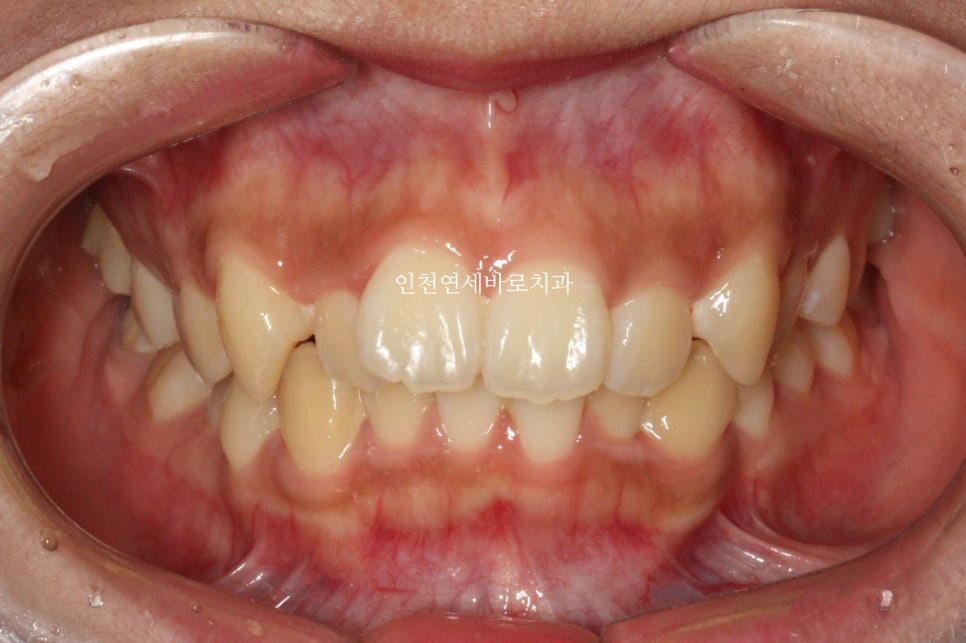

위아래 덧니가 있었고, 깊이 물리는 과개교합 및 중심선의 불일치 보이고 있습니다.

입술의 약간의 돌출감을 개선하고 싶어하셔서

덧니를 비발치로 해결하면서 입술도 후방이동하기로 했습니다.

입술이 많이 들어가진 않았지만, 편안하게 다물어 지는 것이 보이죠?

교정이 약 2년 2개월만에 마무리가 되었습니다.